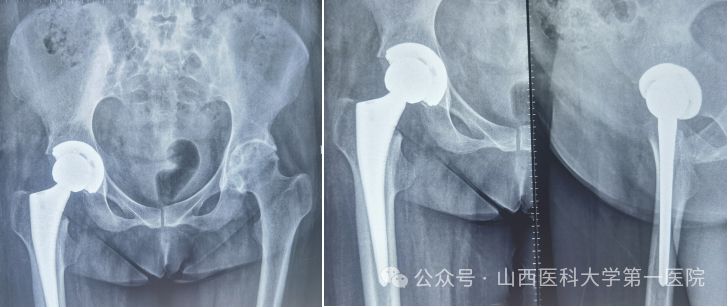

针对患者复杂病情,科室组织多学科讨论。为实现从“站坐难安”到“稳步前行”,杨自权主任团队决定先为患者实施“右侧人工全髋关节置换术”。术中,团队凭借精湛技术,精准处理强直融合的关节结构,在保护周围神经血管的同时,成功植入新的人工关节假体。

强直性脊柱炎伴髋关节病变的置换手术,被誉为骨科领域的“硬仗”。杨自权总结此类患者三大诊疗难点:一是麻醉困难,患者脊柱强直,常无法配合常规麻醉体位;二是解剖变异,长期炎症导致关节周围骨质疏松、肌肉萎缩,手术视野不清,风险极高;三是对手术精度要求更高,假体安放的位置、角度稍有偏差,就会影响术后关节稳定性及使用寿命。

此次手术的成功实施,体现了山医大一院骨科在复杂关节置换领域的深厚积淀和对疑难重症的综合救治能力。杨自权提醒强直性脊柱炎患者:早诊早治,避免关节完全破坏;科学康复,定期复查,确保长期疗效。